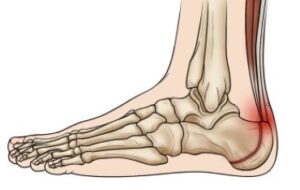

Sever's disease represents inflammation of the heel bone apophyse, and is most often the result of excessive load during intense physical activity. It is common in young athletes aged 8 to 12 years. The pain most often occurs in the heel during or after activity, and may intensify the next day.